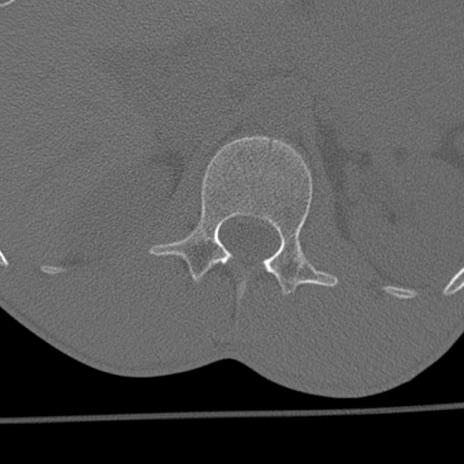

症例3 腰椎CT(横断像)

腰椎CT